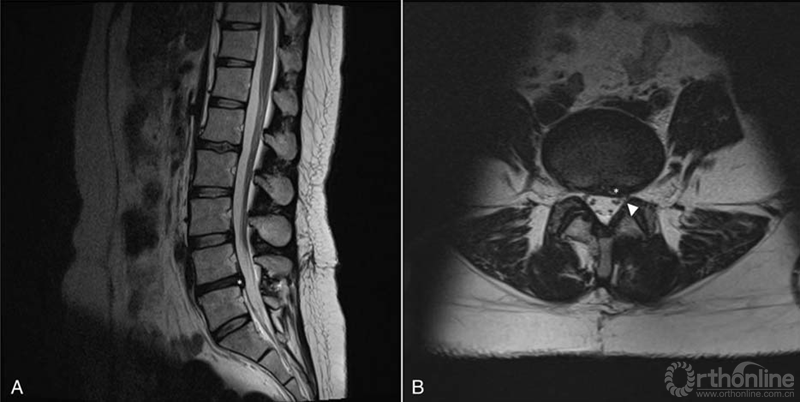

术后患者腰腿疼痛症状立即消失,39周孕龄时顺利产子。术后2年随访,患者未残留任何腰腿部不适(图3A,B)。同时,婴儿发育也未受任何影响。

图3术后2年随访,(A)矢状面和(B)轴向T2加权像显示无椎间盘突出(星号)和神经根压迫解除(箭头)。